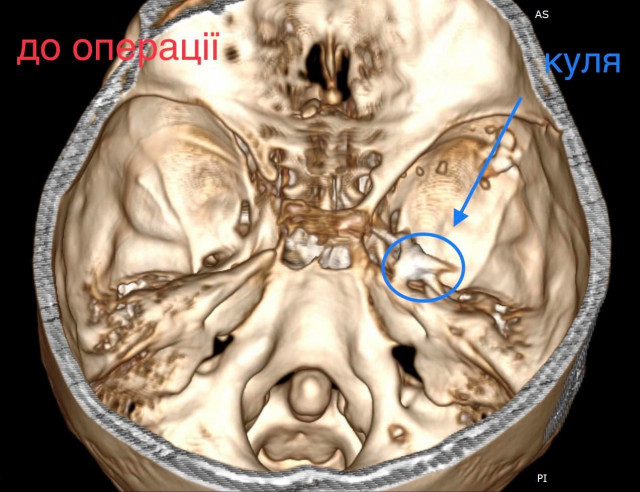

Як повідомив у Фейсбуці нейрохірург дитячої лікарні Михайло Ловга, у хлопця була куля в голові, що призвела до руйнації скроневої кістки та частини головного мозку.

«Ми виконали невідкладну операцію і вилучили стороннє тіло, видалили пошкоджені тканини і відновили цілісність збережених тканин. Добре, що куля зупинилась в 1 см від надзвичайно важливої судини і права скронева частка (яка пошкодилась в результаті травми) – функціонально незначима. Інакше, наш козак був би зовсім іншим, назавжди», – написав Михайло Ловга.